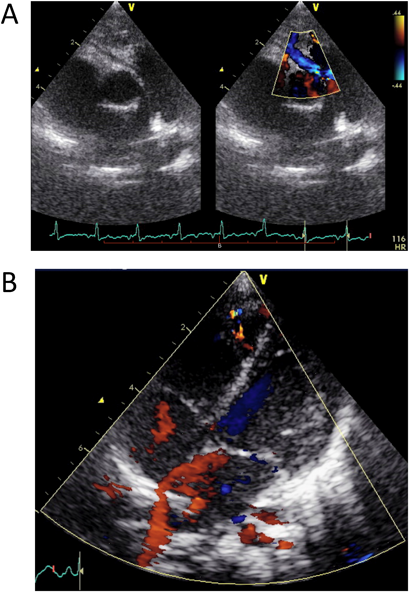

体重増加不良の精査に行った心臓超音波検査が診断につながった右冠動脈肺動脈起始Anomalous Origin of the Right Coronary Artery from the Pulmonary Artery Diagnosed by Echocardiography Performed for Close Examination of Poor Weight Gain